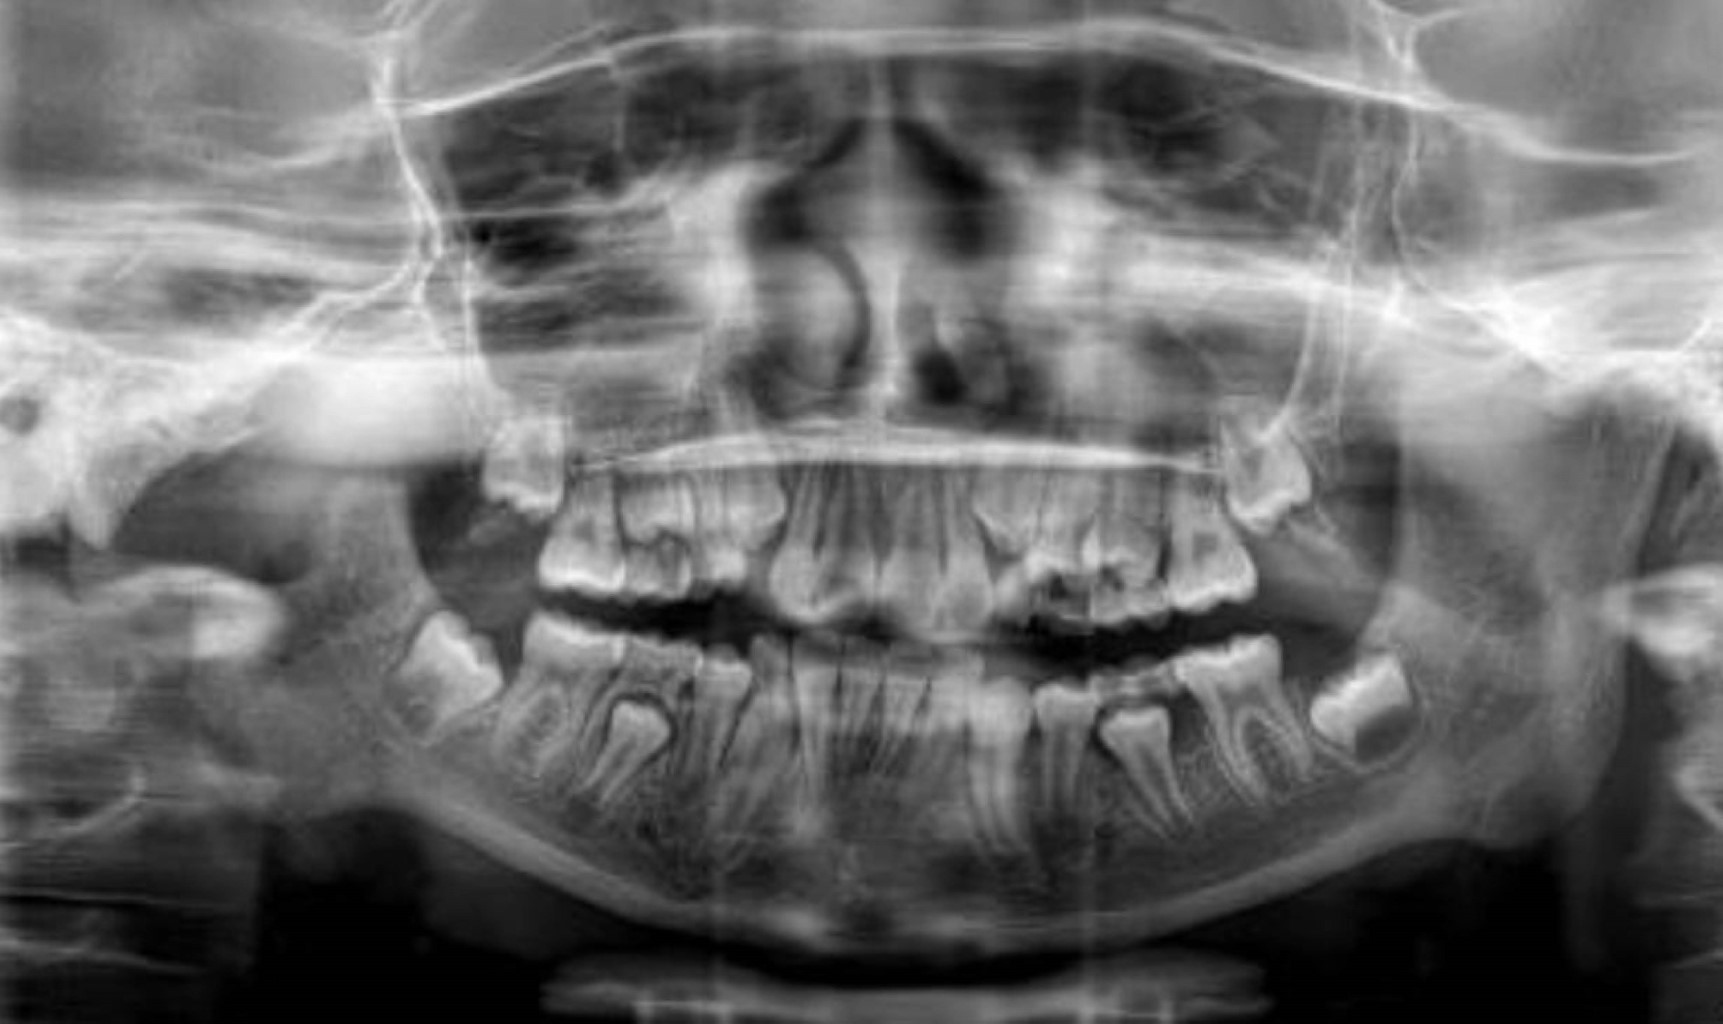

Se presenta paciente femenino de 10 años, al interrogatorio la madre refiere iniciar padecimiento actual al caer de una altura aproximada de dos metros a la edad de cinco años, ocasionando anquilosis de la articulación con disminución de la apertura bucal. Al examen clínico la madre negó alergias, comorbilidades y uso de medicamentos. Extraoralmente no se observaron signos de asimetría facial, a la exploración física e intraoral se encontró trismo severo, apertura bucal de 1 mm, dificultades masticatorias, maloclusión e higiene oral deficiente. Se realizó una tomografía computarizada donde se observa masa anquilótica que afecta la articulación temporomandibular derecha compatible con el tipo 2 de la clasificación de Shawney (Figura 1).